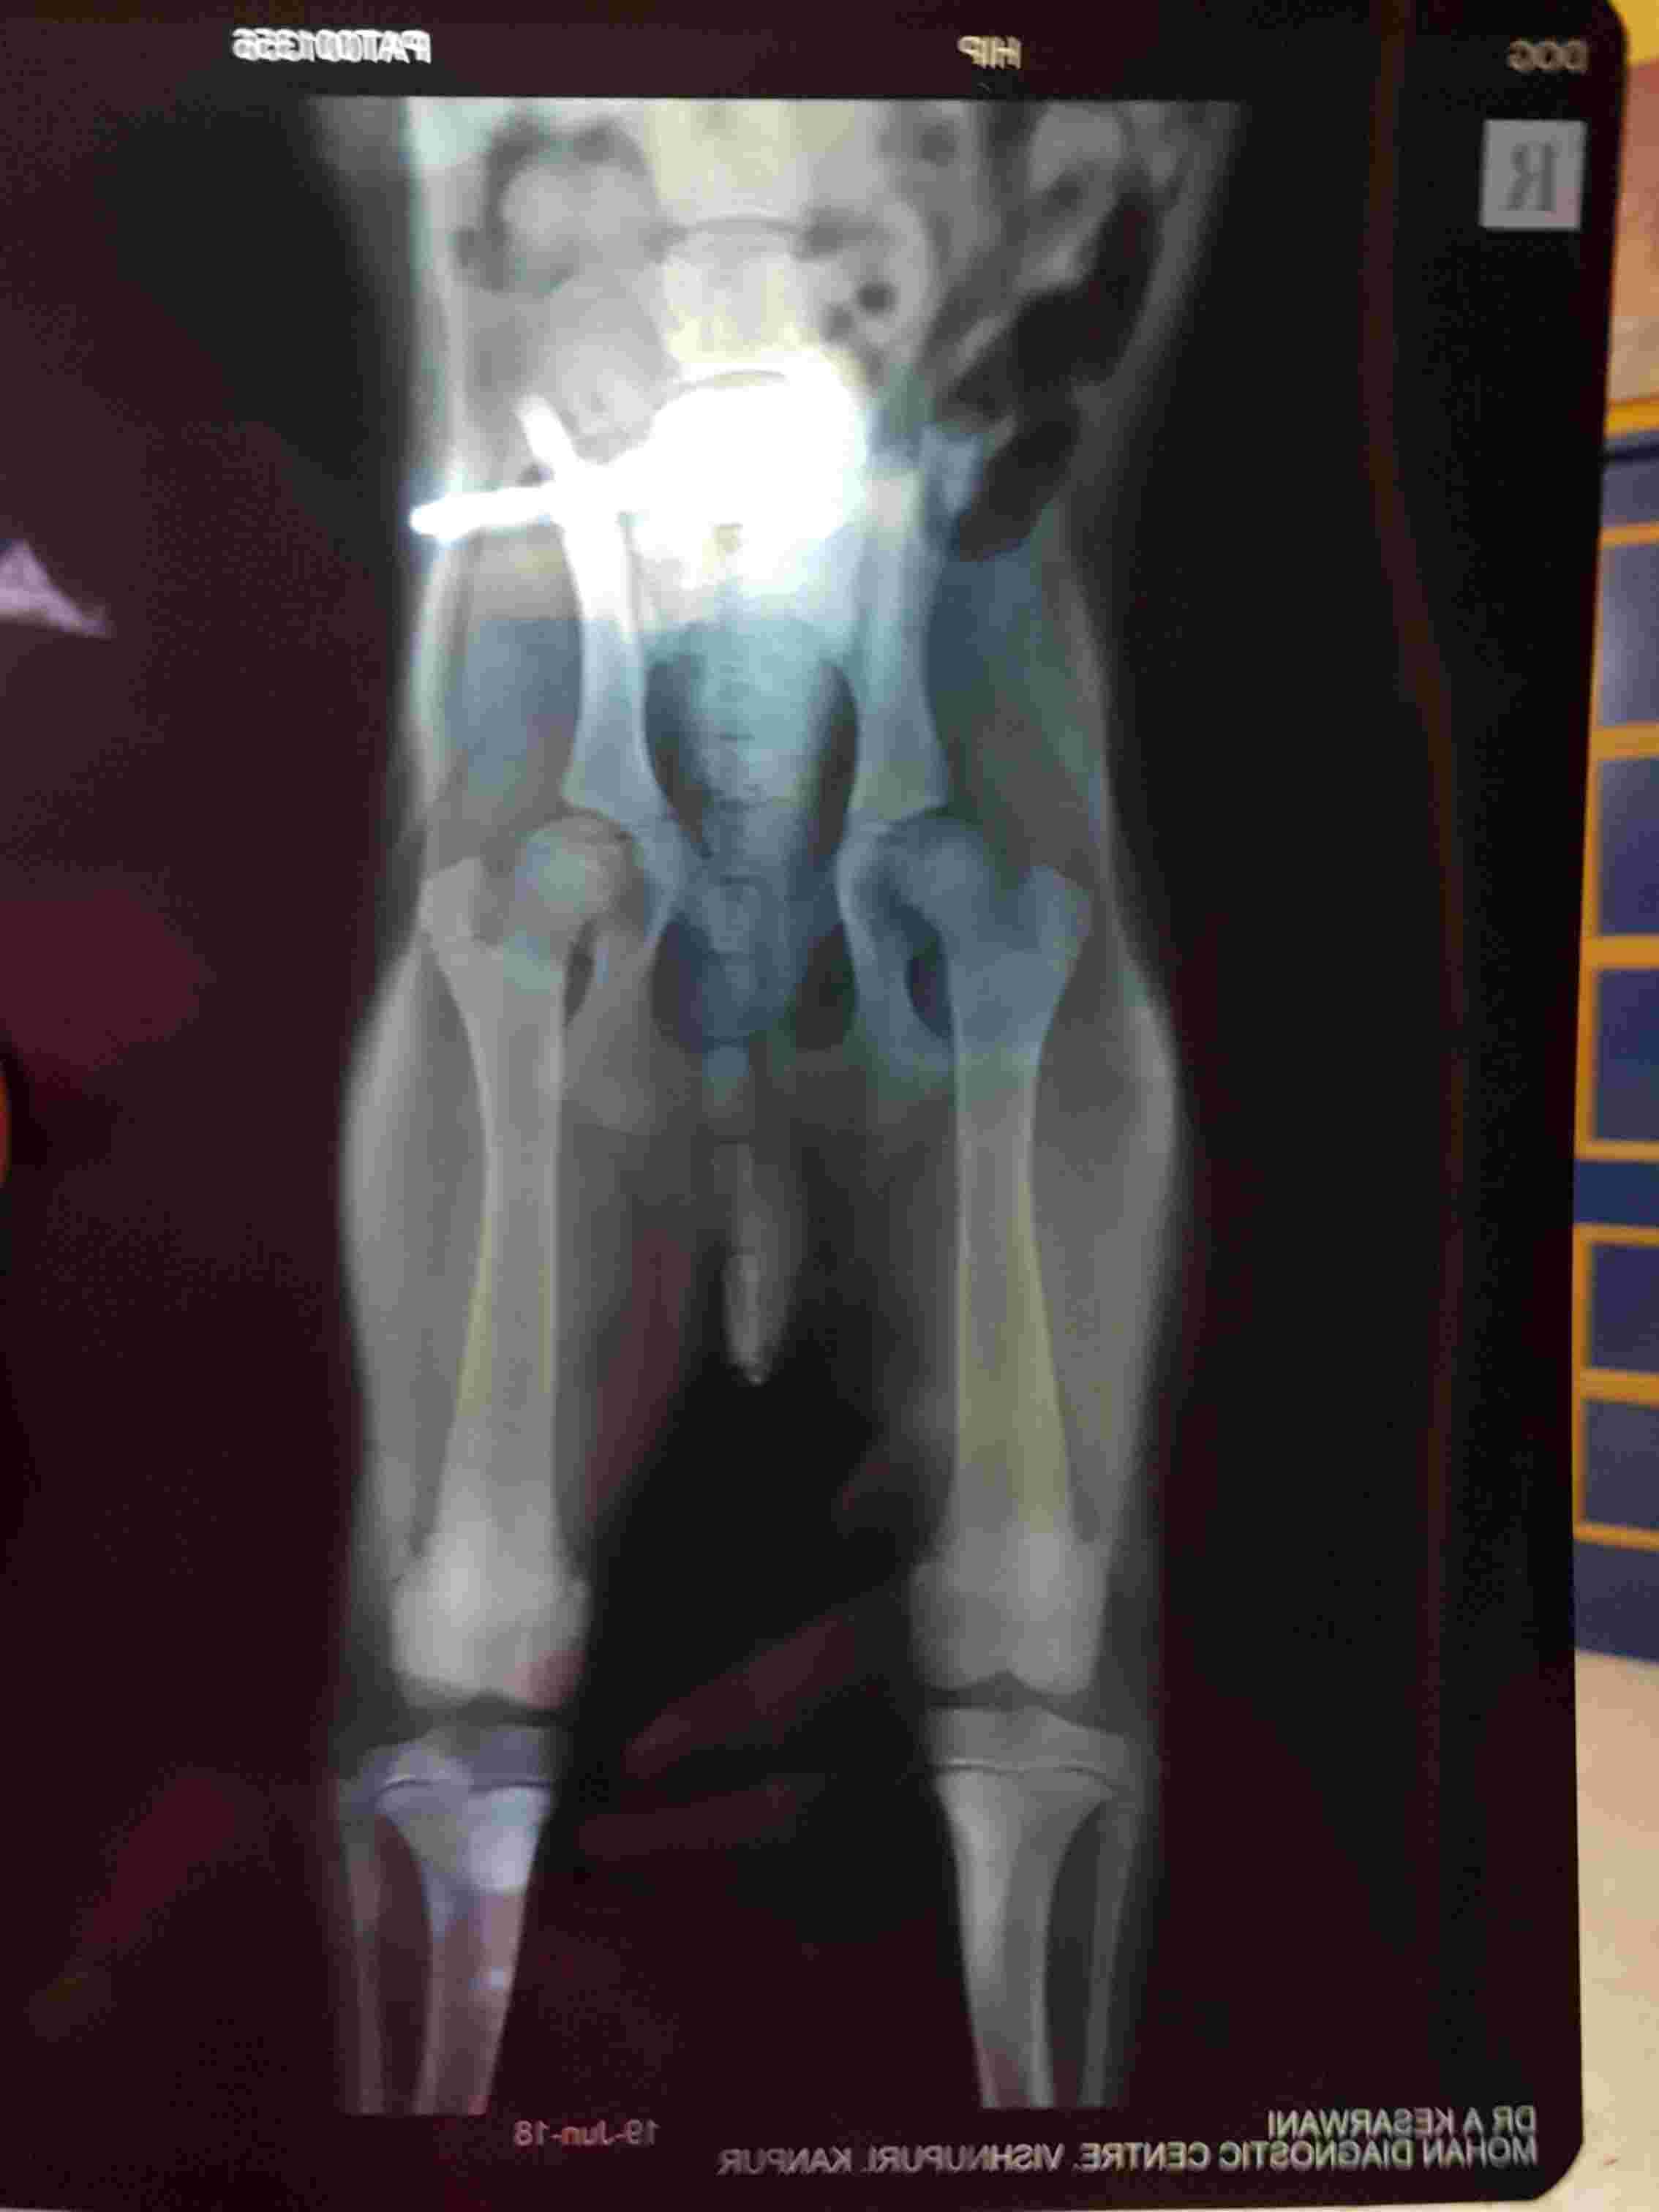

Sudden onset of difficulty rising up and sitting down sits in frog position and does not cry or whine but refuses to take walks doe she have hip dysplasia he is 5 months old lab

Your description of Leo's problem is suspicious of hip dysplasia, but it could also be due to another problem with the hips, lower spine and/or nerves involved. The x-rays are very blurred, so they are difficult to interpret, but the hips appear to have good coverage by the socket. From this information, I would be less suspicious of hip dysplasia and more suspicious of another cause of Leo's problem. It's best to consult with your veterinarian about this, because they will have more information about Leo. If you want a second opinion, then it's best to schedule an appointment with another vet doctor in your area who can physically examine Leo. I hope that helps and all is well with Leo.